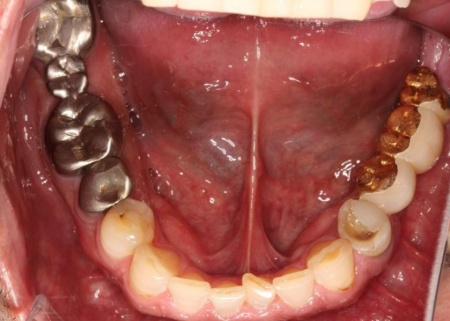

治療前

さらに、劣化してうまく適合していない被せ物、詰め物、既存のインプラントが複数見られ、これらも噛み合わせを乱す原因となっていました。

加えて全体的に歯周病も進行しており、骨が溶けている部分も確認できます。

他院で治療を行った左下奥歯3本のインプラントは、土台をそのまま活かして人工歯だけ作り直し、噛み合わせを調整します。